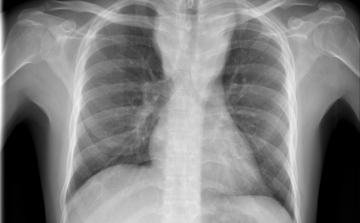

Életmentő tüdőátültetést végeztek az Országos Onkológiai Intézetben

Életmentő tüdőátültetést végeztek egy koronavírus-fertőzés miatt súlyosan roncsolódott tüdejű 41 éves férfin az Országos Onkológiai Intézetben.